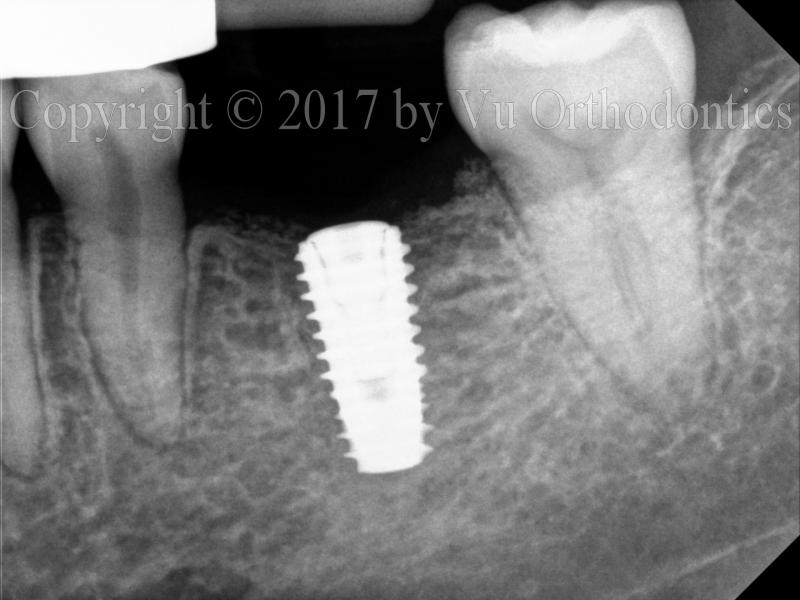

Another example shows a good implant placement (which was done by the author, Fig. 6), using a fully-guided system.

(a)

(b)

Fig. 6. A good implant placement, showing implant and cover screw: (a) PA view, (b) BW view